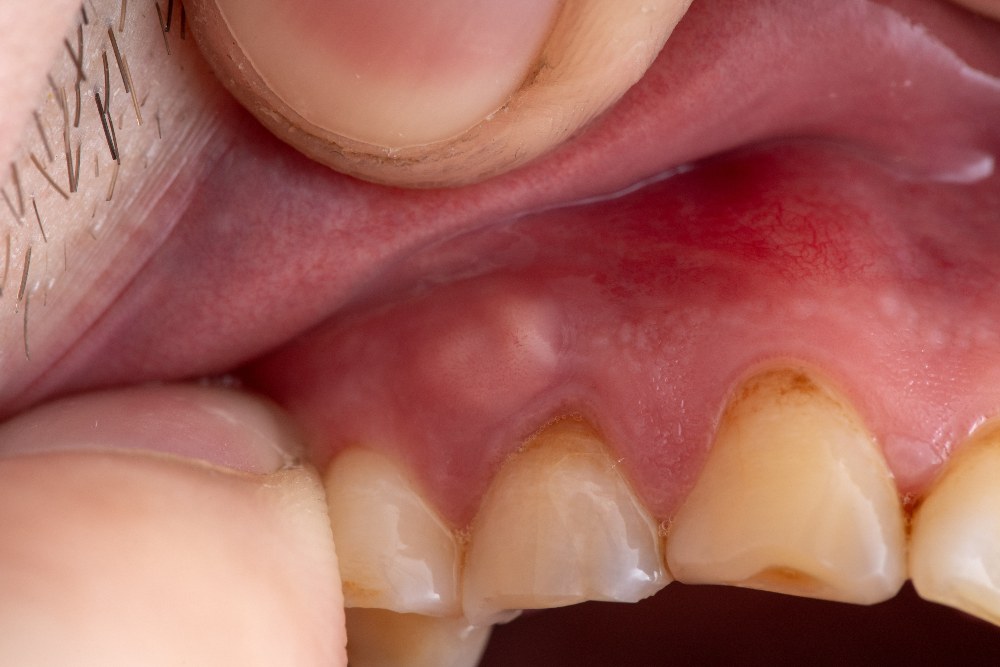

Inflammation and swelling may occur in the affected area, such as the gums surrounding the tooth or the face. The swelling can be accompanied by redness and tenderness.

On the other hand, a periodontal abscess forms in the gum tissues next to the tooth root. It typically arises from an infection that spreads from the gums to the deeper tissues, leading to the formation of an abscess. Periodontal abscesses may cause gum swelling, redness, and tenderness.